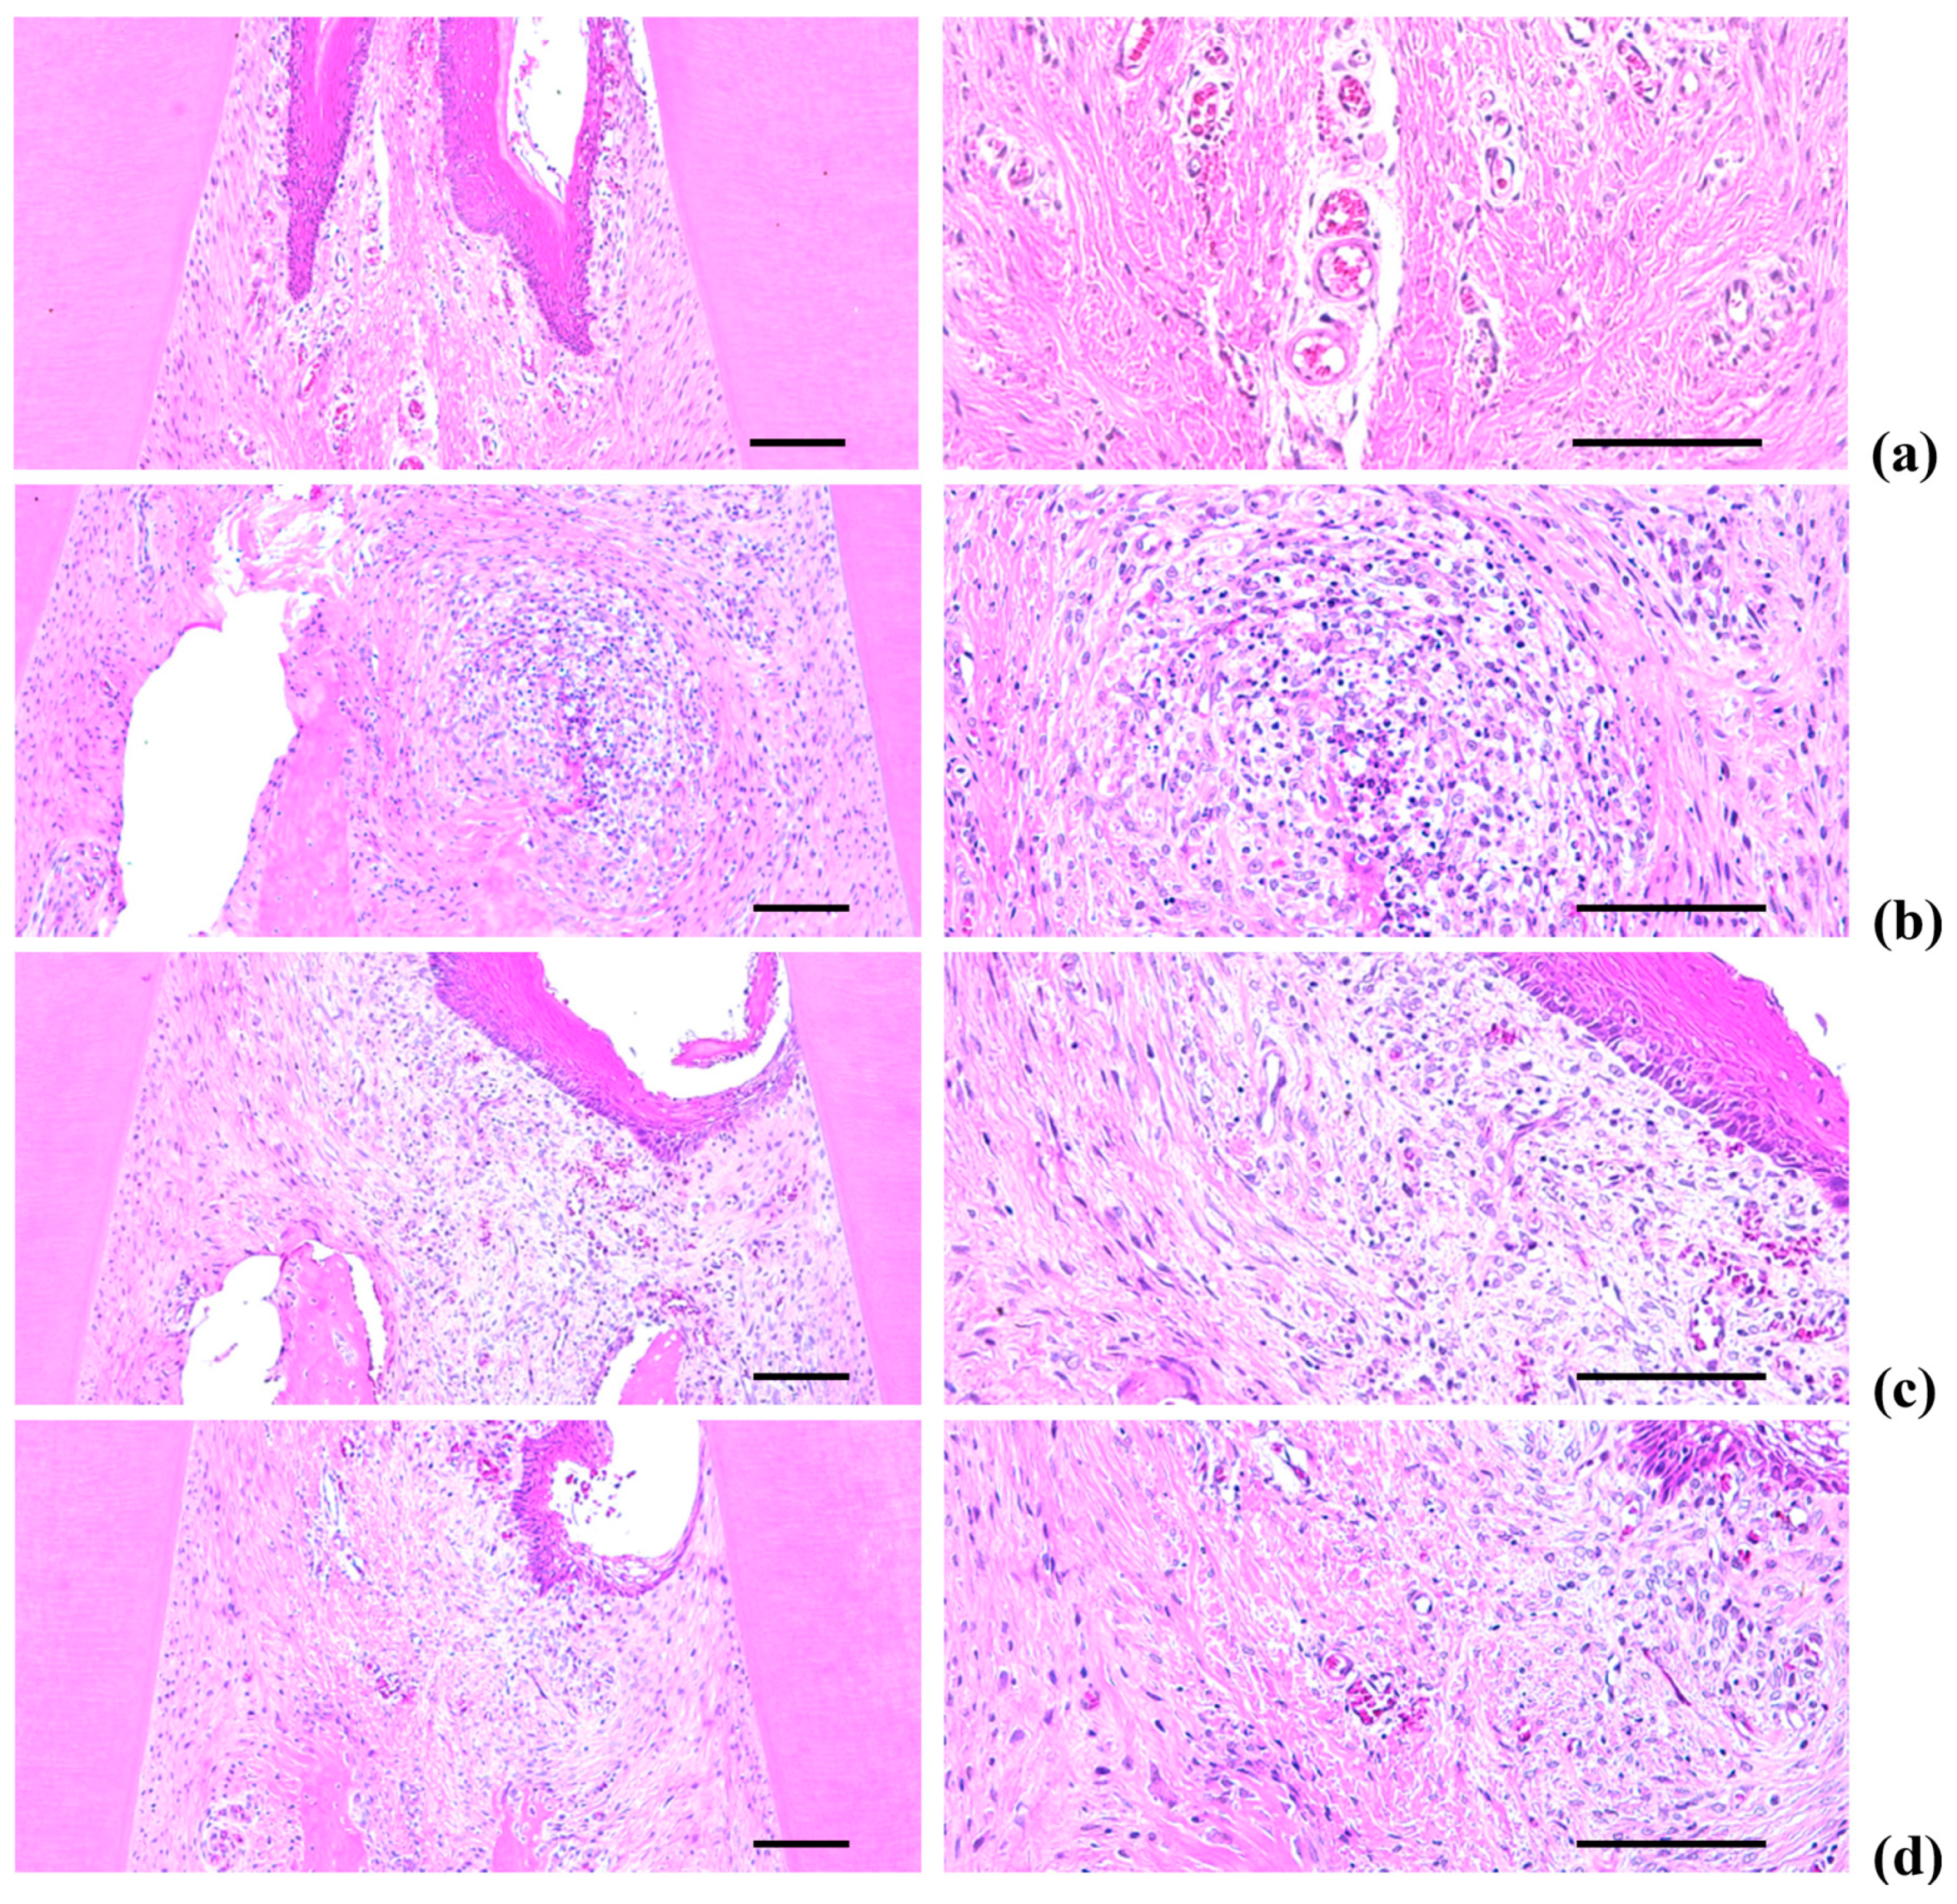

2.5. Histopathology of the Maxillary Regions

Marked increases in inflammatory cell infiltration (mainly polymorphneutrophils (PMNs)) were found in the gingival tissues between the upper left and right incisors in the EPD control, including severe edematous changes; i.e., loosening of the collagen fibers and a loss of compactness. We also observed increased activation of osteoclast cells, as well as increases in the number and percentage of regions occupied by osteoclasts on the alveolar bone surface (OS/BS) in the alveolar bone areas of the EPD control, accompanied by a marked decrease in the volume of osteoid alveolar bone. It follows that periodontitis and related alveolar bone loss was induced by the ligature placements. However, the histopathological evidence for periodontitis, as well as the infiltration of inflammatory cell, the loosening of collagen fiber, the activation of osteoclast cells, and the decrement of the volume of osteoid alveolar bone, was markedly reduced by oral treatment with IND, as well as by topical application of Polycal at all three concentrations compared with the EPD control rats (Table 2, Figure 9 and Figure 10).

Figure 10.

Representative histological images of alveolar bone areas between the upper incisor teeth, taken from Intact or EPD rats around upper left incisor teeth: (a) Intact control (Normal control, non-ligated and distilled water topically applied rats); (b) EPD control (Ligated EPD induced and distilled water topically applied rats); (c) IND (Ligated EPD induced and indomethacin 5 mg/kg orally administered rats); (d) Polycal-H (Ligated EPD induced and Polycal 50 mg/mL solution topically applied rats); (e) Polycal-M (Ligated EPD induced and Polycal 25 mg/mL solution topically applied rats); and (f) Polycal-L (Ligated EPD induced and Polycal 12.5 mg/mL solution topically applied rats). All H & E stain. Scale bars = 120 µm.

2.5.3. Changes on the Alveolar Bone Volumes

Significant (p < 0.01) increases of the alveolar bone volumes were detected in all test substance treated rats as compared with EPD control, respectively. Especially, all three different concentrations of Polycal topical applied rats showed increases of alveolar bone volumes between upper left and right incisor teeth where ligation was placed as compared with EPD control rats (Table 2, Figure 10).

2.5.4. Changes on the Osteoclast Cells

As with previous EPD studies [42,43], periodontitis leads to marked infiltration of inflammatory cells, as well as edematous changes in the gingival tissues between the upper incisors. In addition, we found evidence of absorption of the alveolar bones due to osteoclast cell activity via histopathological observations. Increases in histological scores are associated with infiltration of inflammatory cells and alveolar bone damage [4,23,44]. The infiltration of inflammatory cells, decreases in collagen-occupied regions related to edematous changes, decreases in bone volume, increases in the number of osteoclast cells and increases in the ratio OS/BS that were detected via our histomorphometrical analyses are consistent with previous reports [7,8]. These histopathological changes related to periodontitis and alveolar bone loss were reduced markedly with oral administration of IND, as well as by topical application of Polycal at all three concentrations, in which the response was concentration response trend.